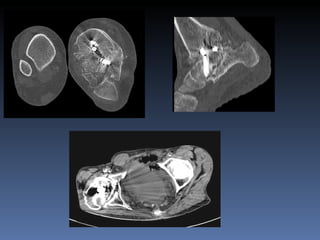

Tomografia Computarizada (TC) Tubo de rayos x que rota alrededor del pte Capacidad de obtener imagenes axiales Reconstruccion en otros planos y 3D Mejor para corteza osea y calcificaciones Buena para evaluar fracturas comminutas pelvis calcaneo Muneca

Tomografia Computarizada (TC) Desventajas Dosis de radiacion al paciente Artefactos  por  metales Pobre caracterizacion de partes blandas